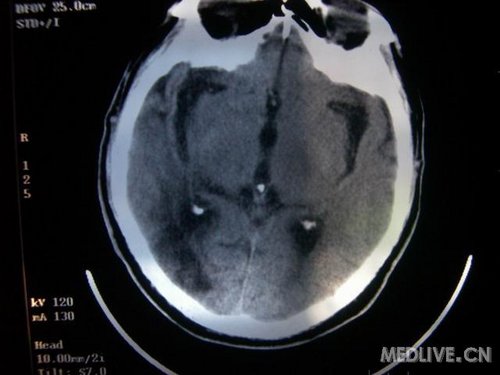

病人男性 73岁 市民 以“幻听、幻视两天,言语含糊、精神错乱一天”入院。

两天前无诱因出现幻听、幻视,描素眼前有彩色的圆圈,听见有人说话(但说什么不详),一天前出现胡言乱语,言语含糊,精神错乱,问话不答,行走略有不稳,来我院就诊,门诊头CT检查:(下面有片)入院后查体不合作,表情淡漠,问话不答,大致检查了一下,颅神经未见明显异常,颈软,右手活动似忽略差。其他检查不配合。脑电图:广泛轻-中度异常。

既往史:半年前曾患“右侧脑梗塞”但无明显后遗症,生活能自理,无高血压、糖尿病、心脏病史。

此次入院时的片子: